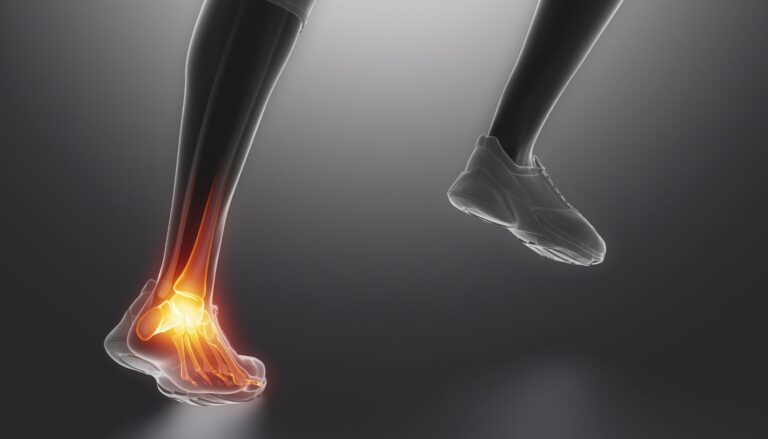

Co tak naprawdę dzieje się w naszym ciele, gdy mówimy o zroście kości po operacji haluksa? Choć proces ten może wydawać się skomplikowany, jego zrozumienie jest.